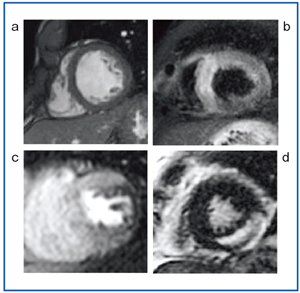

図1 心臓MRIプロトコル a:シネMRI、b:Black blood MRI c:パフュージョンMRI、d:遅延造影MRI

図1 心臓MRIプロトコル

a:シネMRI、b:Black blood MRI

c:パフュージョンMRI、d:遅延造影MRI

当院では、Signa HDxt 1.5T(GE社製)を心臓MRIに用いている。心臓MRIの年間検査数は約180件、主な依頼理由は心筋症をはじめとする心不全である。心臓MRIルーチン撮像プロトコルは、black blood MRI、シネMRI、パフュージョンMRI(安静時)、遅延造影MRIである(図1)。負荷時のパフュージョンMRIは、現状では施行していない。